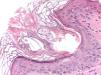

Additional TestsA 2-mm punch biopsy was taken from the left preauricular region. Histologic examination revealed the presence of 2 dilated follicular infundibula, with foci of compact hyperkeratosis, associated in both cases with the presence of a mite (Fig. 3). A mild perivascular lymphocytic inflammatory infiltrate was observed in the underlying dermis.